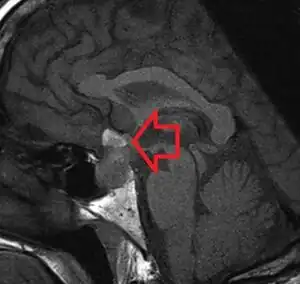

| MRI showing a pituitary macroadenoma with bleeding within the tumor resulting in pituitary apoplexy[1] | |

It is recommended that magnetic resonance imaging (MRI) scan of the pituitary gland is performed if the diagnosis is suspected; this has a sensitivity of over 90% for detecting pituitary apoplexy; it may demonstrate infarction (tissue damage due to a decreased blood supply) or hemorrhage.[6] Different MRI sequences can be used to establish when the apoplexy occurred, and the predominant form of damage (hemorrhage or infarction).[7] If MRI is not suitable (e.g. due to claustrophobia or the presence of metal-containing implants), a computed tomography (CT) scan may demonstrate abnormalities in the pituitary gland, although it is less reliable.[6] Many pituitary tumors (25%) are found to have areas of hemorrhagic infarction on MRI scans, but apoplexy is not said to exist unless it is accompanied by symptoms.[6][9]